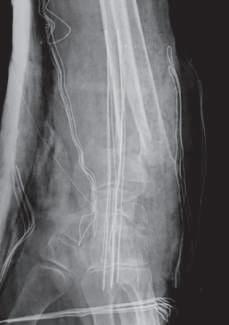

Lesões Ósseas

Palavras-chave: fraturas ósseas.

Keywords: bone fractures.

Introdução

O esqueleto do corpo humano é constituído por 206 ossos que são responsáveis pelas mais diversas funções, nomea damente: proteção dos órgãos internos, suporte mecânico, regulação da homeostasia mineral, funções hematopoiéti cas. Ao contrário dos outros tecidos no corpo humano que após lesão regeneram com tecido cicatricial, o tecido ósseo regenera com osso novo, indistinguível do osso original.

Devido à sua elevada área de exposição, o esqueleto apre senta, frequentemente, sinais de traumatismos, advindo daí a sua importância numa perspectiva médico-legal, quer em termos de patologia, quer de clínica forense. Após uma le são óssea, há a formação de um hematoma e uma resposta inflamatória que vai induzir a formação de osso novo por osteoblastos locais. Há a constituição de uma matriz co lagenosa e a diferenciação de células mesenquimatosas, com a formação de cartilagem. Os condrócitos proliferam, hipertrofiam e segregam fatores que vão induzir a ossifi cação da cartilagem, com a conversão de cartilagem em osso novo – ossificação endocondral. Este osso é remode lado pela ação combinada de osteoblastos e osteoclastos, dando origem a osso maduro de acordo com as linhas de stress/tensão (Clohisy et al., 2009). Dependendo do timing da lesão óssea, assim, poderemos ter lesões ante mortem, peri mortem e post mortem.

A presença de um calo ósseo, denotando assim um osso que teve tempo para maturar, aponta para uma lesão ante mortem. Já uma lesão que não apresenta sinais de conso lidação pode ter tido origem peri mortem ou post mortem A constituição do osso é alterada após a morte, com perda de água e da sua elasticidade, tornando assim o osso mais quebradiço, o que vai influenciar as características das lesões ósseas post mortem

Nas lesões peri mortem, encontra-se uma coloração mais uniforme e a presença de fraturas incompletas, em espiral e de tensão-compressão, frequentemente mais oblíquas. Nas lesões post mortem, em que o osso se encontra mais seco por desidratação, a coloração pode ser mais heterogénea

(por exposição ao meio envolvente), as superfícies de fratu ra vão apresentar-se mais regulares, com bordos retos, e as fraturas serão mais longitudinais e transversais irregulares (Cunha & Pinheiro, 2005/2006).

A forma e a aparência das lesões ósseas podem refletir não só a direção, a área, a velocidade, a massa e a forma do objeto produtor da lesão, mas também as próprias ca racterísticas inatas do tecido ósseo, como o seu conteú do mineral, as características físicas do osso em questão ou eventuais alterações patológicas do mesmo (Cunha & Pinheiro, 2005/2006). Sendo uma combinação de matéria orgânica e inorgânica, o tecido ósseo é capaz de sofrer de formação elástica e plástica antes da falência. Mas uma vez iniciada a fratura, esta propagar-se-á através do osso até que a energia seja dissipada.

Existem três tipos principais de lesões: cortantes, contun dentes e perfurantes. Quando há uma combinação destas, podemos ter lesões mistas, como as perfuro-contundentes provocadas por projéteis de armas de fogo. Por regra, os diferentes tipos de lesões apresentam características típi cas dos instrumentos responsáveis pelas mesmas, apesar de o mesmo instrumento poder ser responsável por diferen tes tipos de lesões e a mesma lesão poder ser provocada por instrumentos diferentes.

36.1

Lesões cortantes e corto-contundentes

As lesões provocadas por instrumentos cortantes vão de pender das características da sua lâmina, o que pode per mitir identificar o instrumento responsável pelas mesmas. É possível a análise da impressão provocada no osso – dos entalhes ósseos e dos seus bordos, paredes e pavimen tos – e identificar padrões nas estrias que permitam dis tinguir o tipo de instrumento. A análise das estrias através da microscopia eletrónica permite identificar imperfeições específicas das lâminas, o que pode levar à identificação do instrumento específico responsável por uma determi nada lesão. A partir da análise das lesões, pode ser ainda

© PACTOR 473

36

possível identificar a direção do movimento e os padrões de corte (Bartelink et al., 2001; Ciallella et al., 2002; Saville et al., 2007; Symes, 1992; Symes et al., 2001).

Assim, podemos encontrar lesões produzidas por instru mentos de gume liso, serrilhado ou complexo, simples ou duplo. Quando além da ação do gume o instrumento apre senta um peso elevado, vamos ter lesões de características mistas (corto-contundentes), como acontece com lesões

provocadas por machados, espadas ou catanas (Figura 36.1), que atuam pela ação do peso e do gume cortante (Humphrey & Hutchinson, 2001; Lewis, 2008).

As lesões ósseas do tipo cortante ou corto-contundente ocorrem em grande número no contexto de acidentes de trabalho com trauma dos membros superiores, nomeada mente das mãos (Figura 36.2).

Fig. 36.1 Lesão por catana

Fig. 36.2 Lesão por serra